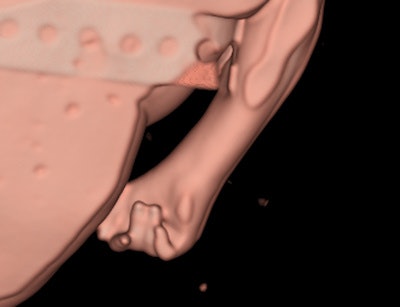

Surface-rendered CT image of a 38-week-fetus shows the intact palate. All images courtesy of Dr. Sarah Constantine.Constantine and her colleagues plan to approach the local ethics committee again soon with their interim findings to see if they can persuade them to let them use a single consent form because this would give access to around three or four fetuses per week on average. They are also looking at the possibility of injecting diluted contrast into the fetal heart under ultrasound guidance to improve visualization of the heart.

Surface-rendered CT image of a 20-week-fetal hand demonstrates the typical overlapping digits of trisomy 18.Constantine and her colleagues investigated the value of dual-energy MDCT as part of the inquiry into fetal abnormalities and pregnancy losses in the second and third trimesters, and early neonatal period. The study was approved by the Women's and Children's Hospital Network Human Research Ethics Committee. Patients were recruited while giving consent for conventional autopsy.